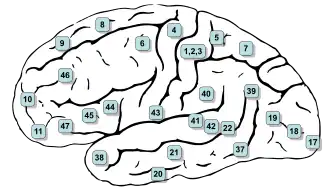

Image

-

Animation.

Animation. -

front view.

front view. -

Lateral view.

Lateral view. -

Medial view.

Medial view.